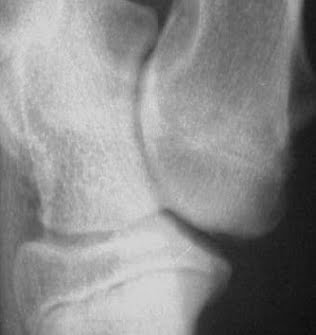

Si manifesta con zoppia dell’arto anteriore di 1° – 2° grado che comincia dal 4°-8° mese d’età in poi, in stazione, alterazione della postura con atteggiamento antalgico con i gomiti in fuori Alla palpazione si percepisce un’ectasia della capsula articolare, a livello del muscolo anconeo Nei casi piu’ gravi si percepisce un’ispessimento capsulare con dolorabilita’ in flesso- estensione. Esame radiografico medio-laterale neutra a 120° medio-laterale flessa a 45° antero-posteriore obliqua 15° in pronazione La mancata unione ha 3 stadi di gravità in funzione del grado di distacco del processo anconeo.

1° stadio la linea di separazione non ha una radiotrasparenza completa ed il processo appare in posizione normale

2° la linea di separazione ha una zona di radiotrasparenza completa, ma il processo appare ancora in posizione normale

3° stadio, oltre alla zona di radiotrasparenza completa, più ampia, riassorbimento osseo del processo con erosioni del suo profiloi ,con spostamento del processo leggermente in alto.